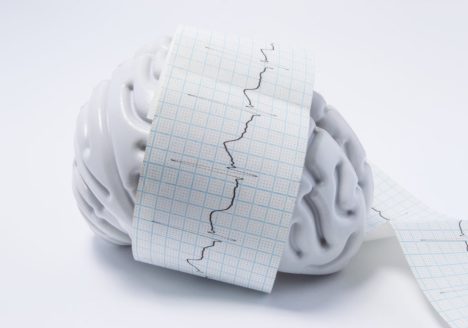

تفاوت میان صرع و تشنج چیست؟

تشنج ها اتفاقهای مجزایی هستند که در نتجیه فعالیت الکتریکی غیر طبیعی در مغز به وجود می آیند. ایجاد تشنج ها می توانند علل متعددی داشته باشد از جمله رخدادهای واحد مثل…